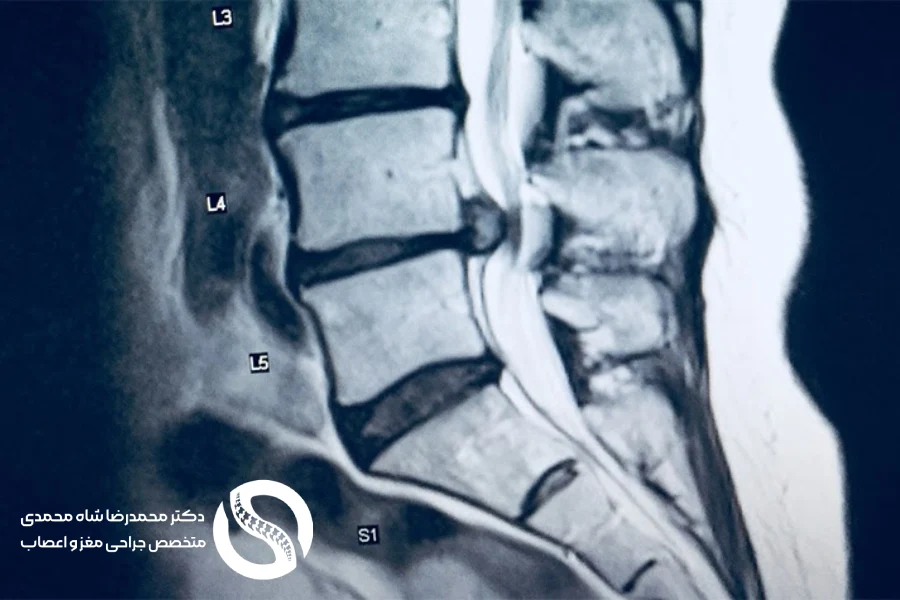

ابزارهای تشخیصی تصویربرداری برای تشخیص تنگی کانال نخاعی کمر

برای تأیید تشخیص و برنامهریزی درمان، پزشک از ترکیب سابقه بالینی و ابزارهای تصویربرداری مانند: تصویربرداری اشعه ایکس، MRI، سیتی اسکن و سیتی مایلوگرام استفاده میکند.